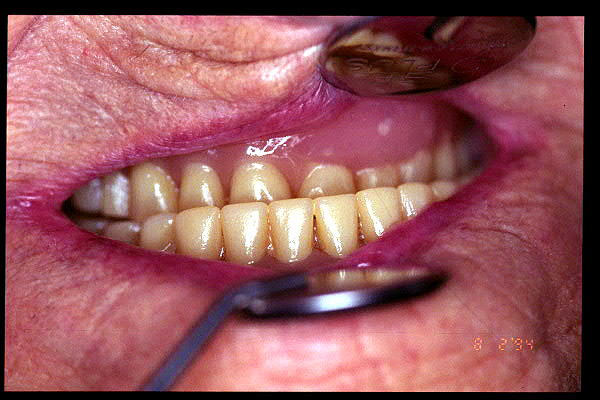

CM Prótesis del año 1950